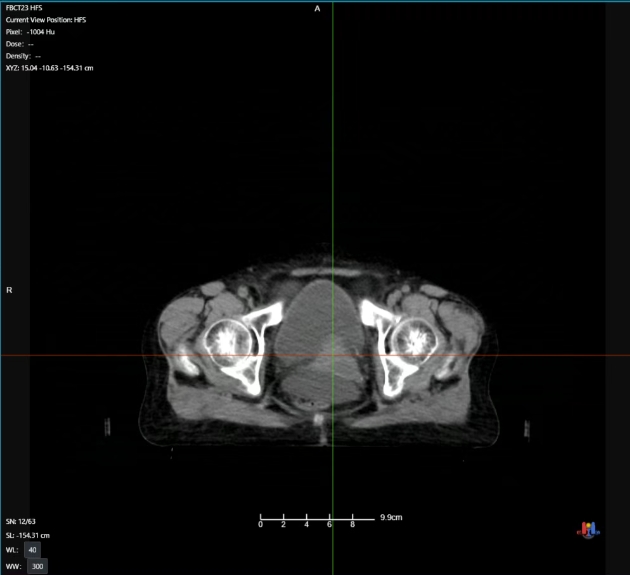

放疗结束时病灶影像

整个放疗治疗周期中刘阿姨反馈为基本无无明显不适。通过治疗期间CT影像可发现,随着放疗次数增加病灶逐步减小,效果明显,最终该病灶基本消失!